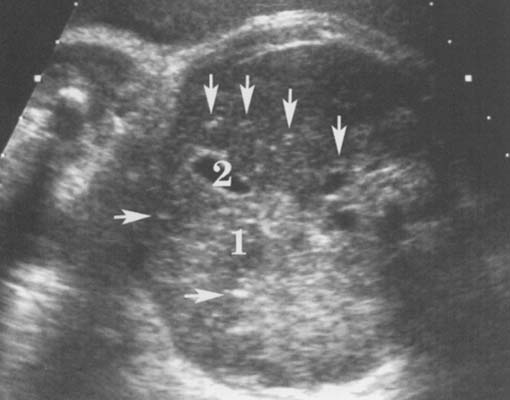

Séméiologie échographique :

Les données post natales montrent que seulement 10 à 20 % des enfants sont symptomatiques et sont donc susceptibles de développer des anomalies décelables in utero. Il est cependant probable que seuls les fœtus présentant les atteintes les plus sévères présenteront des signes échographiques. L'échographie ne montrerait en pratique des signes d'infection que chez 5% des enfants atteints (93).

La séméiologie échographique décrite par les différents auteurs comporte les signes suivants :